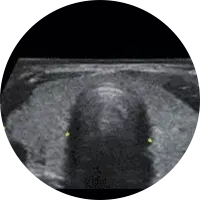

A Ecografia é um método de estudo e diagnóstico que permite, devido à emissão de ondas sonoras ou ultra-sons, examinar diversas áreas do corpo e órgãos e confirmar um diagnóstico clínico. Pode, portanto, ser usada para fins muito diversos como a observação ao pormenor do fígado, a vesícula biliar, rins, baço, tiróide, próstata, artérias e veias (Ecodoppler), entre outros. O exame de ecografia não causa nenhuma dor.

Existem vários tipos de preparação para os diferentes tipos de ecografia.